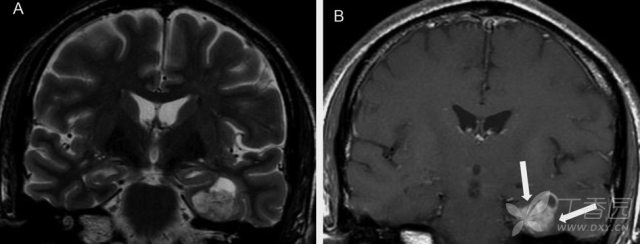

图 2:34 岁 FCD 女性患者可见 Transmantle 征;A:T2WI 可见右侧额叶局部信号增高伴皮层增厚,灰白质界限不清;B:FLAIR 上可见条带状异常高信号从皮质延伸至侧脑室

MRI 主要表现为局灶性皮质增厚,灰、白质分界模糊,白质异常信号,脑回形态异常,脑回白质萎缩,脑叶发育不全,邻近蛛网膜下腔扩大。FLAIR 及 T2WI 序列较为敏感,常表现为灰白质界限不清和皮质下白质高信号,可见病灶沿一个脑回的冠或脑沟的底向脑室延伸并逐渐变细,有学者将此现象命名为 Transmantle 征,常见于 FCD II 型。